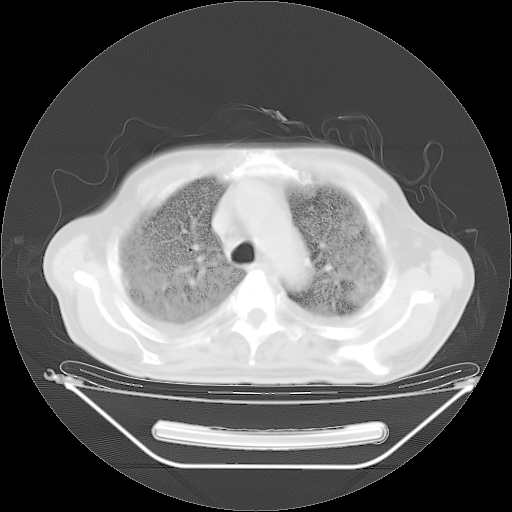

今天复查肺部CT,发现双肺广泛磨玻璃样改变。所以我把3月19日和5月9日相隔50天的肺部CT上传。请大家会诊。

2009年3月19日肺部CT片。

2009年3月19日肺部CT

大致读了系列胸部CT:纵隔窗无明显异常,肺窗:从4、27至今:主要是双肺中下野外带可见毛玻璃样改变,目前处于急性肺泡炎阶段,至于原因考虑1、结替组织或胶原血管性疾病所致?2、恶性疾病如恶组在肺部所致的表现或细支气管肺泡癌?3、药物或其它原因如肺蛋白沉着症所致肺泡炎目前不太可能?总之,明天就去请我院的呼吸科、感染科、血液科和临免专家会诊哈。